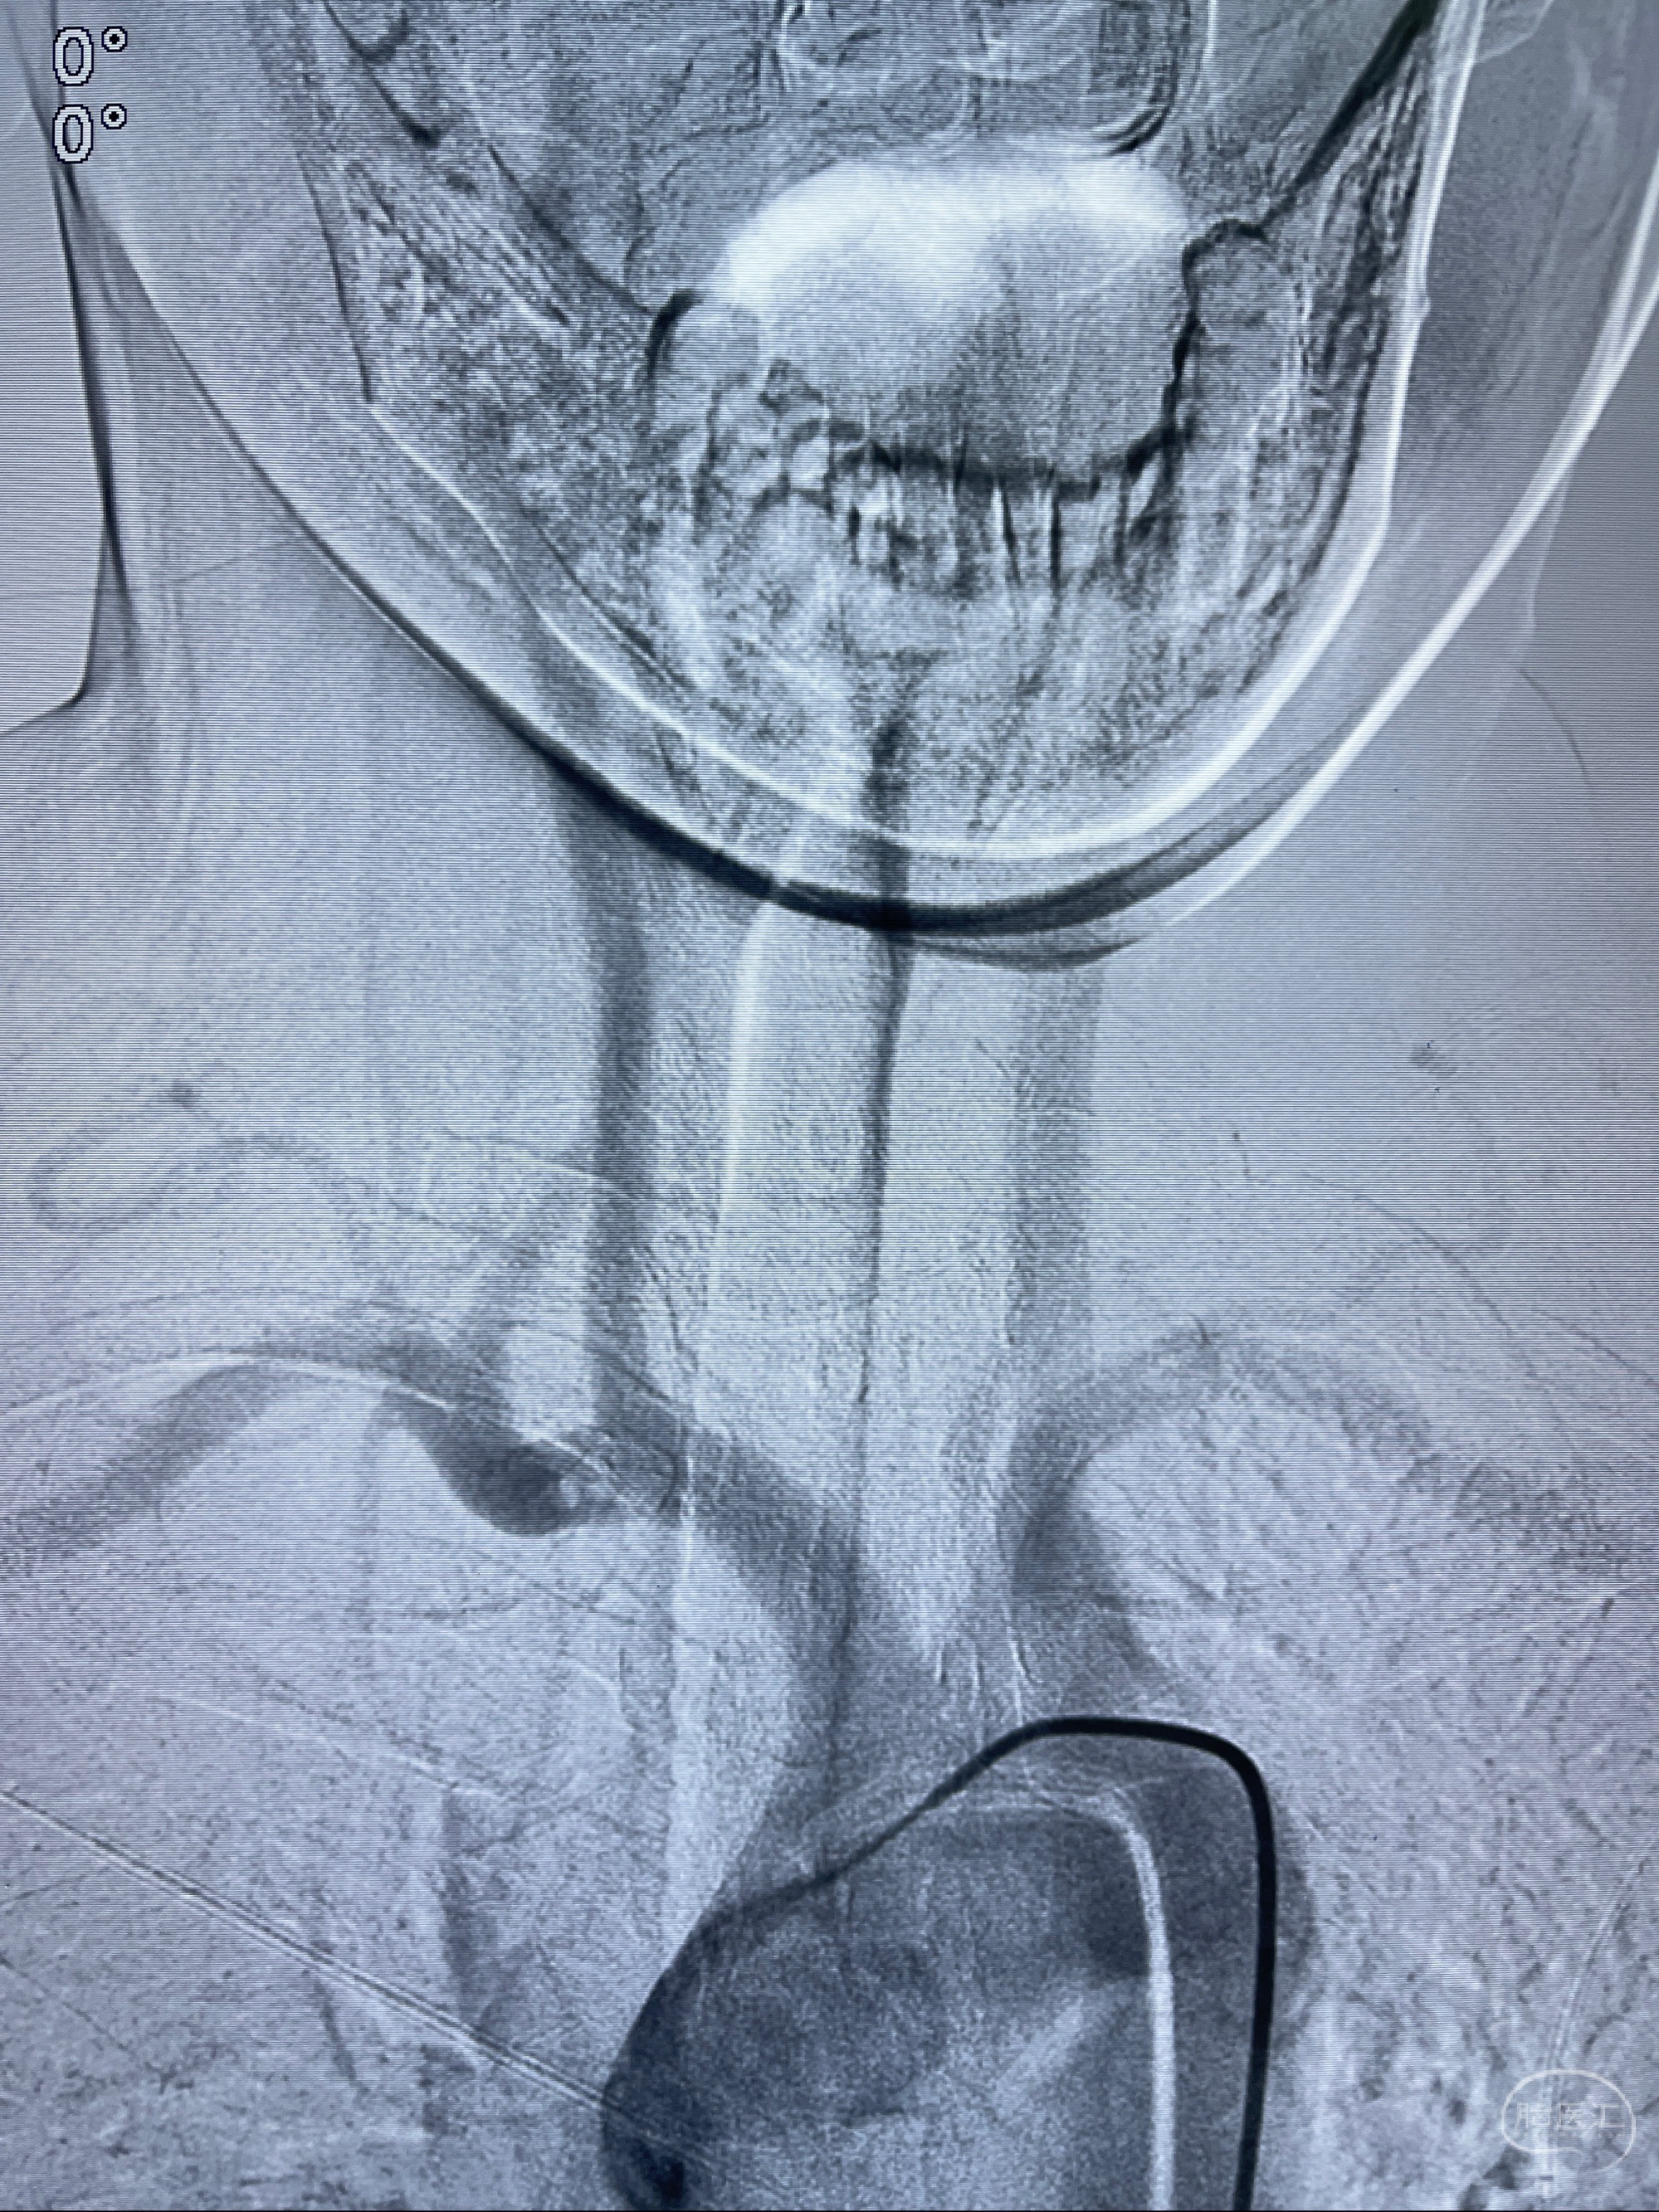

2023-08-14DSA:

左侧大脑中动脉动脉瘤,约2.6-2.8-3.4-2mm大小(瘤颈部、瘤体部、瘤高)